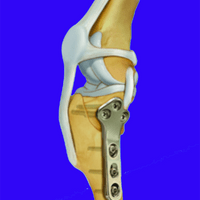

Chirurgia ortopedica

Nella nostra struttura si offre un servizio di chirurgia ortopedica tramite l’utilizzo di diverse tecniche operatorie, quali i fissatori esterni e l’utilizzo di placche e viti (fissazione interna), per il trattamento delle fratture .Per il trattamento della Rottura del legamento crociato craniale del ginocchio, si effettuano le metodiche piu’ moderne come: la TTA POROSA (tibial tuberosity advancement) e la TPLO (osteotomia livellante del piatto tibiale) .

Ci occupiamo anche delle patologie chirurgiche legate alla Displasia di rotula.